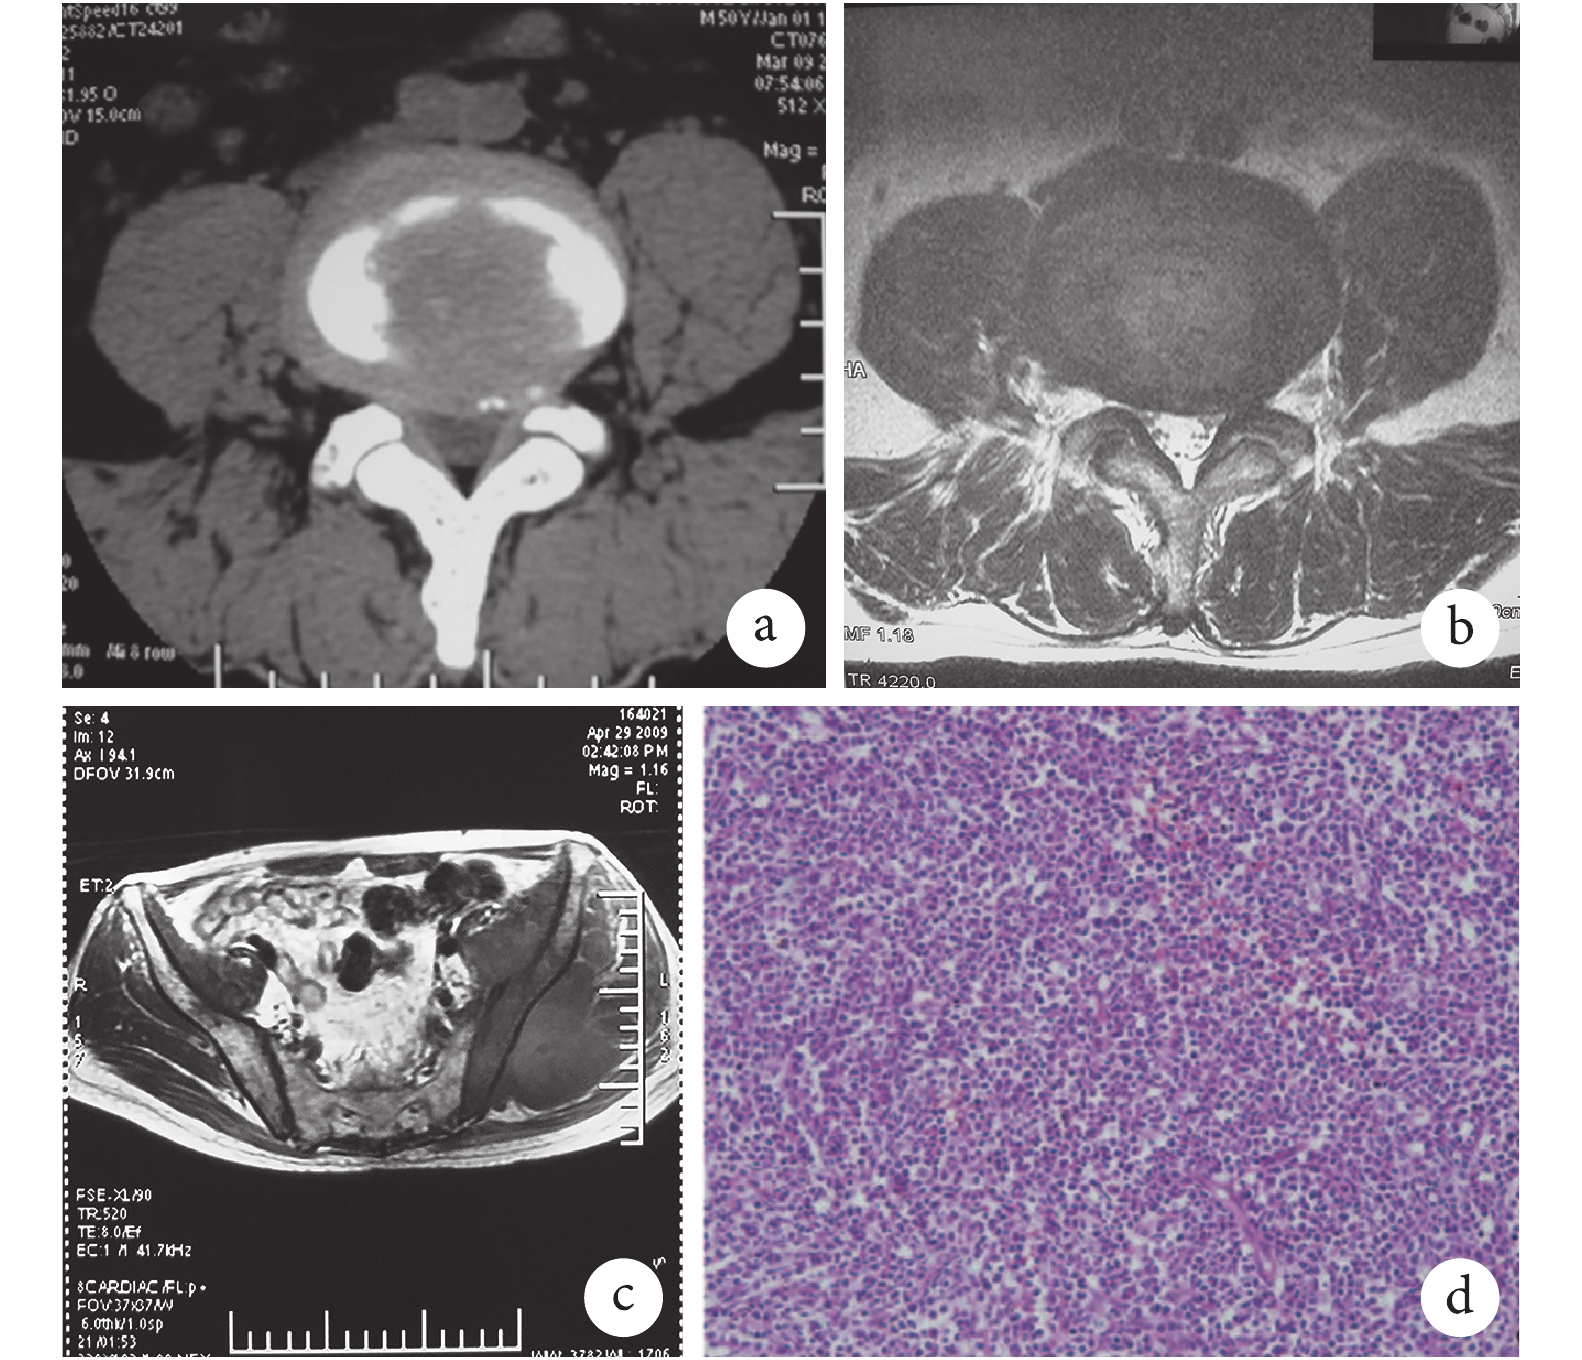

患者 男,50 歲,因“左下肢放射痛 3 個月”于 2009 年 3 月入院。患者于 3 個月前無明顯誘因出現左下肢放射痛,疼痛從左側臀部至大腿后方、小腿前外側、足背,于外院行腰椎間盤 CT 檢查,診斷為 L4、5 椎間盤突出癥;給予甘露醇、地塞米松等常規藥物治療,治療期間左下肢放射痛明顯緩解,停藥后疼痛復發,為進一步治療轉入我院。患者患急性粒細胞白血病,于 2003 年 7 月行骨髓移植,本次入院時為粒細胞白血病“完全緩解期”。入院查體:左側臀部較右側稍腫脹,局部按壓可觸及深部腫物,重力按壓時可誘發左下肢放射痛,疼痛視覺模擬評分(VAS)為 6 分;左側小腿前外側足背、足底皮膚感覺較右側明顯減退;翹?肌力明顯減弱,肌力約 3 級,踝關節跖屈肌力稍減弱,肌力約 4 級;左下肢直腿抬高試驗(+),加強試驗(+),左側梨狀肌緊張試驗(+),左側跟腱反射較右側減弱,下肢病理征(–)。腰椎 X 線片示腰椎代償性側彎,骶椎腰化;腰椎間盤 CT 示 L4、5 椎間盤突出合并鈣化,L5、S1 椎間盤突出(圖 1a);腰椎間盤 MRI 示 L4、5 和 L5、S1 椎間盤突出伴神經根受壓,L4、5 為重(圖 1b)。根據查體顯示,單純腰椎間盤突出無法完全解釋患者癥狀和體征,遂加行骨盆 MRI 檢查,發現左側臀部、坐骨神經走行區局部實性占位性病變(圖 1c);聯合超聲定位后穿刺活檢,病理檢查提示粒細胞肉瘤(granulocytic sarcoma,GS)(圖 1d)。結合患者急性粒細胞白血病史,考慮粒細胞白血病髓外復發。由于患者同時合并腰椎間盤突出癥,突出位置也偏向左側,因此考慮腰椎間盤突出和左側臀部 GS 可能同時參與導致左下肢放射痛。與患者及家屬溝通后先行藥物治療,經血液科會診后轉入該科治療,給予正規全身化療及局部放療 1 個月后,患者左下肢放射痛明顯緩解。治療后隨訪 3 個月,患者自述左下肢疼痛較局部放療前緩解,VAS 評分為 3 分,自覺效果滿意不愿進行后續治療,未再接受手術治療。

a. 腰椎間盤 CT;b. 腰椎間盤 MRI;c. 骨盆 MRI;d. 病理檢查(HE×200)